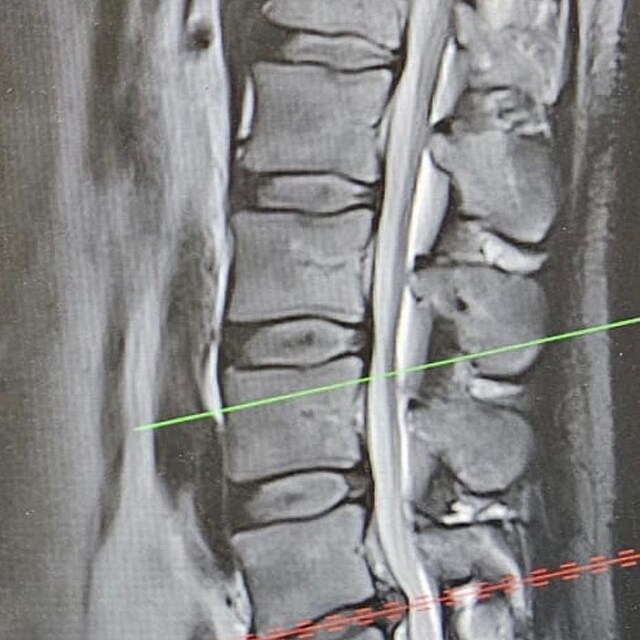

„Dostávám silné kapačky, užil jsem si svou oblíbenou magnetickou rezonanci během neděle a probíhá už i fyzioterapie. S léčbou jsem začal ve čtvrtek po návratu ze státní návštěvy v Bratislavě. Začátkem příštího týdne bych měl mít ještě jeden drobný zákrok, abych se vyhnul operaci, která časem asi bude nutná, ale rekonvalescence by nyní byla příliš dlouhá. Kdy budu z nemocnice propuštěn, to neumím odhadnout,“ vzkázal nám.